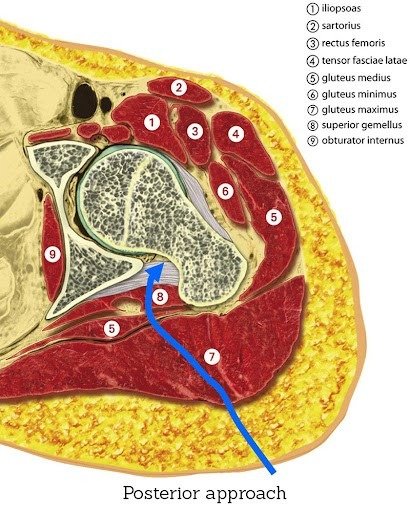

The posterior approach: a versatile option for complex or revision cases

The posterior approach accesses the joint from the back of the hip and remains a well-established and widely used technique. It provides excellent visibility of the joint, which is especially useful when dealing with:

- Abnormal bone anatomy

- Significant joint deformity

- Revision procedures where old implants must be removed

- Stiffness or contractures that limit joint access

Although the posterior approach involves releasing some muscles and soft tissue, these are repaired during closure. With the right surgical technique and rehabilitation, long-term outcomes remain excellent.